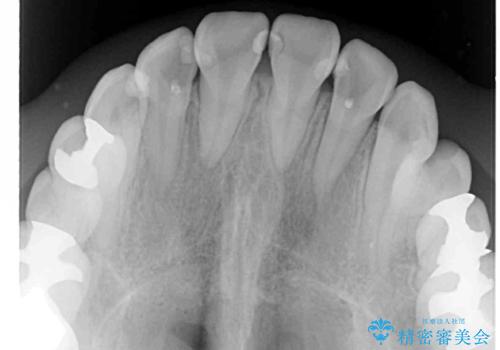

- 上下のデコボコと奥歯の咬みにくさを気にして来院された患者様です。

上顎骨の幅が下顎骨よりも小さいので、拡大装置により骨幅を広げて上下関係を改善し、その後インビザラインにて歯並びを整えることとしました。

上下の骨幅を改善したことで、スムーズに歯列矯正を行うことができました。